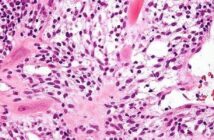

Ennek érdekében a kutatócsoport több mint 1000 Lyme-kóros beteg genetikai mintázatát elemezte, és hasonlította össze nem fertőzött személyekével. “A cél az volt, hogy olyan specifikus génváltozatokat azonosítsunk, amelyek közvetlenül összefüggésbe hozhatók a betegséggel” – fejtette ki Javier Botey-Bataller, a cikk társszerzője. “Úgy tűnik, munkánkat siker koronázta, mivel valóban sikerült azonosítanunk egy különleges, eddig ismeretlen génváltozatot (rs1061632) a Lyme-kóros betegeknél. Ez a polimorfizmus a KCTD20 és az ETV7 gének eQTL-je (expression quantitative trait loci) volt, ami az mTOR-útvonal és a citokinválaszok upregulációjával, valamint alacsonyabb Borrelia-ellenes antitest-termeléssel társult.”

A kutatócsoport különböző sejtbiológiai és immunológiai vizsgálatokat végzett, hogy kiderítse, milyen konkrét élettani következményei vannak ennek a genetikai hajlamnak.